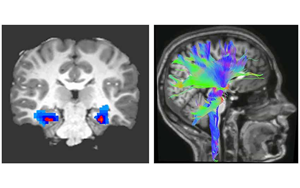

Nature Medicine:一種新的強迫癥神經生物標志物

貝勒醫學院和德克薩斯兒童醫院最近的一項研究確定了一種特定的神經活動模式,作為一種新的生物標志物,可以準確預測和監測接受深部腦刺激(DBS)治療的強迫癥(OCD)患者的臨床狀態,深部腦刺激是一種迅速出現的治療嚴重精神疾病的方法。